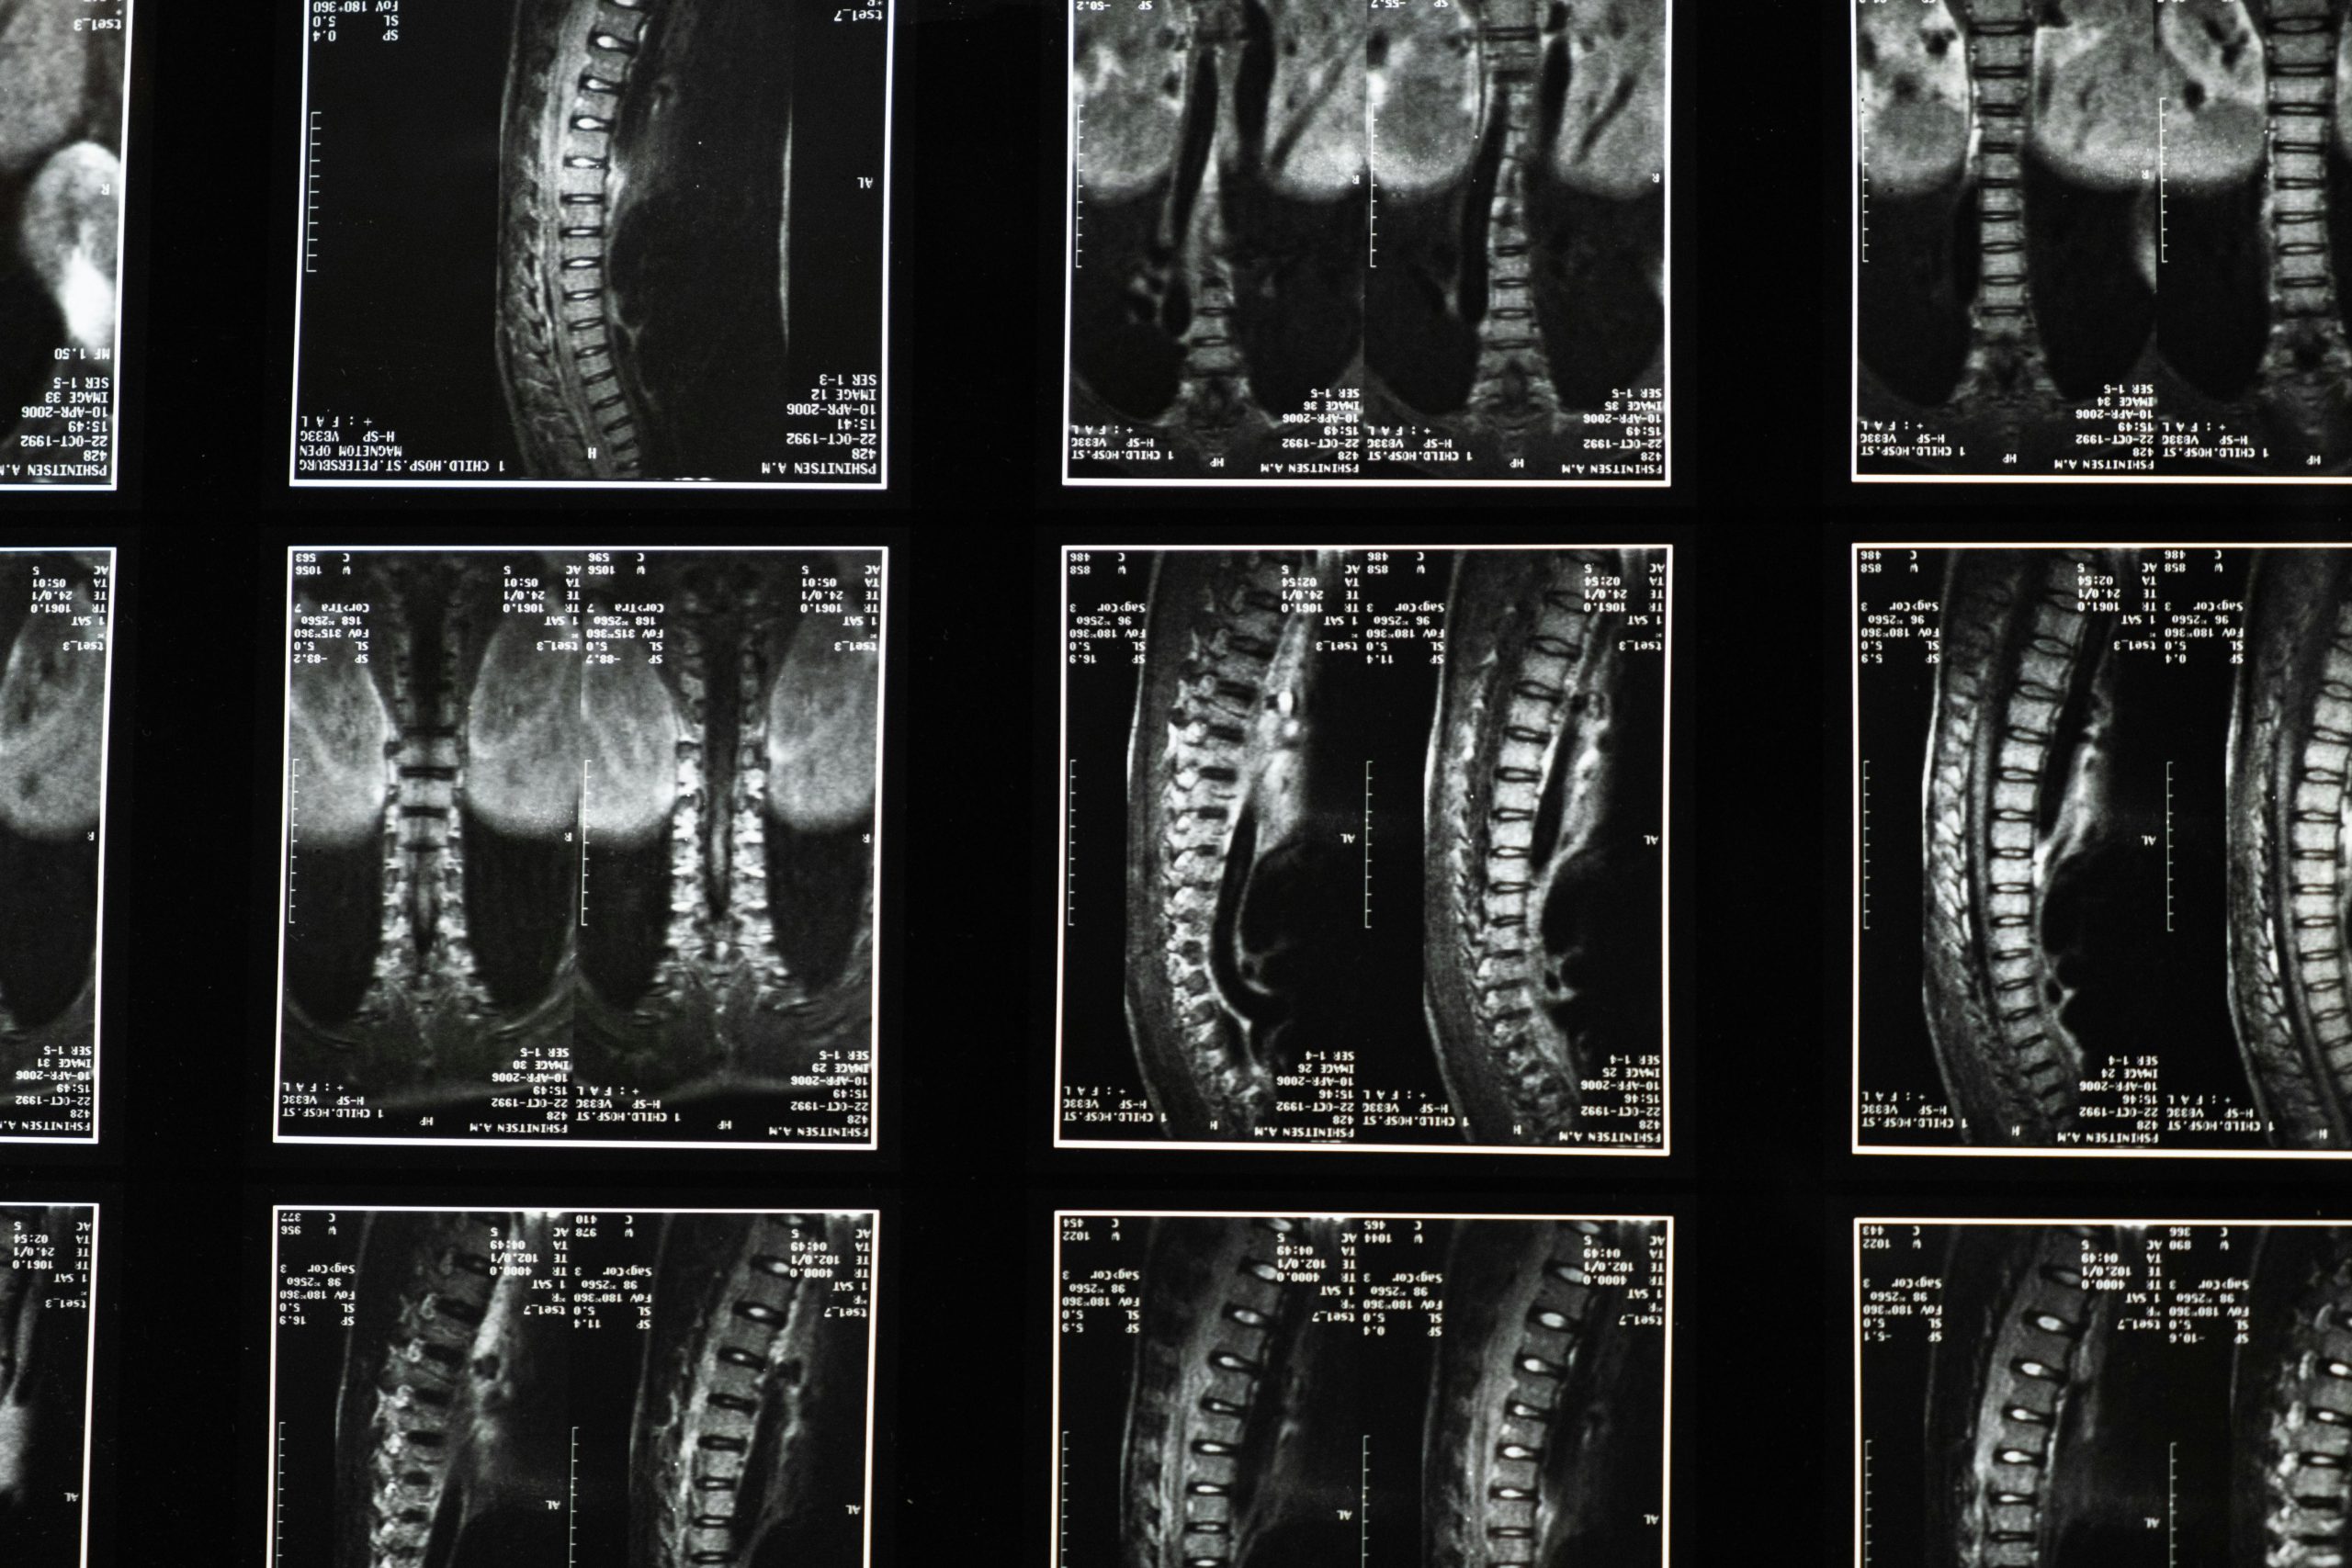

Spinal stenosis is a condition characterized by the narrowing of the spinal canal, which houses your spinal cord and nerves. This narrowing can be caused by bone spurs, thickened ligaments, or bulging/herniated discs, putting direct pressure on sensitive nerve structures.

When the spinal canal narrows, it can compress the delicate spinal cord or the nerve roots branching off of it. This compression is often a result of age-related changes such as osteoarthritis, degenerative disc disease, or the thickening of spinal ligaments. The persistent pressure on nerves leads to the debilitating symptoms that can severely limit your walking distance and overall activity. Many traditional treatments for stenosis primarily focus on symptom management rather than directly addressing the issue of reduced space within the spinal canal. Our approach aims to create more space non-invasively.